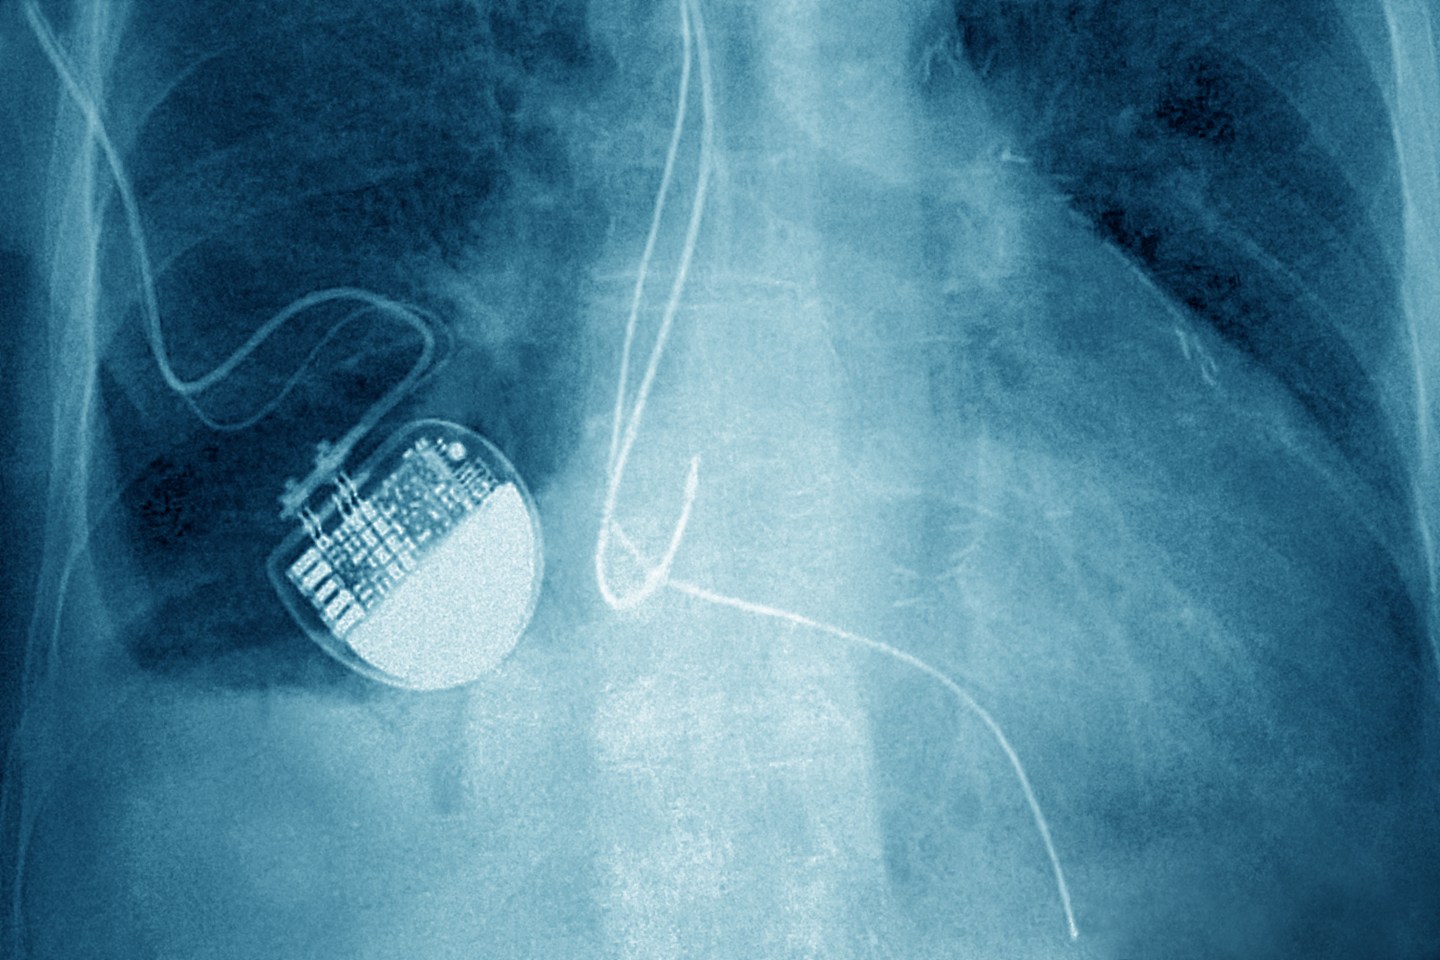

Ross Compton appeared in an Ohio court on Tuesday to face two felony charges of aggravated arson and insurance fraud after a fire at his home on Sept. 19. Police said Compton, who has told local news outlets that he is innocent, uses a pacemaker, which police mined for data to help determine whether he took items from the home and tossed them out a window during the fire, as he’s claimed. A cardiologist who reviewed his heart rate and cardiac rhythms for signs of exertion when he raced to save his belongings, has said that his version of events during the fire are “highly improbable,” according to the Associated Press.

Soon after his house caught fire, Compton called 911 and said that he “grabbed a bunch of stuff, threw it out the window,” according to local news outlet WLWT5. He said that he packed suitcases filled with items, broke his bedroom window, and threw the suitcases safely outside. Although police reportedly found evidence of gasoline on Compton’s clothing and shoes, the pacemaker data was critical to the investigation.

“It was one of the key pieces of evidence that allowed us to charge him,” Lt. Jimmy Cunningham told WLWT5 in an interview last month. Police argued that his condition, coupled with the pacemaker data, suggests his description of what happened is false.